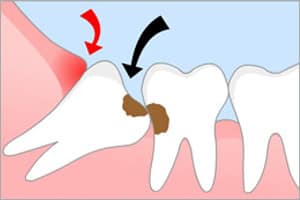

Медиальный наклон часто приводит к развитию кариеса в соседней семёрке из-за разрушения эмали и накопления остатков пищи в щели между верхушками. Щёчный наклон часто сопровождается травмированием слизистой щеки, что может привести к образованию опухоли. При дистальном наклоне требуется удаление зуба мудрости.

Также существует воспалительное заболевание, называемое перикоронитом, которое возникает при длительном прорезывании верхушки зуба мудрости. При этом зуб мудрости может прорезываться в течение года или даже нескольких лет. В результате травмирования десны появляется «кармашек», в котором скапливаются остатки пищи и развивается воспаление.